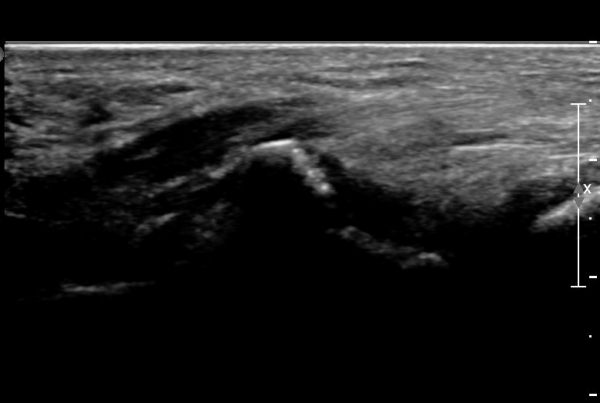

ŽÃËÀÚ¸¦ ¾à°£ ¸»´ÜÀ¸·Î À̵¿ÇÏ´Ï ¿¬ºÎÁ¶Á÷ ºÎÁ¾ÀÌ ´õ¿í ½ÉÇÏ°Ô °üÂûµÇ°í(»çÁø 2),